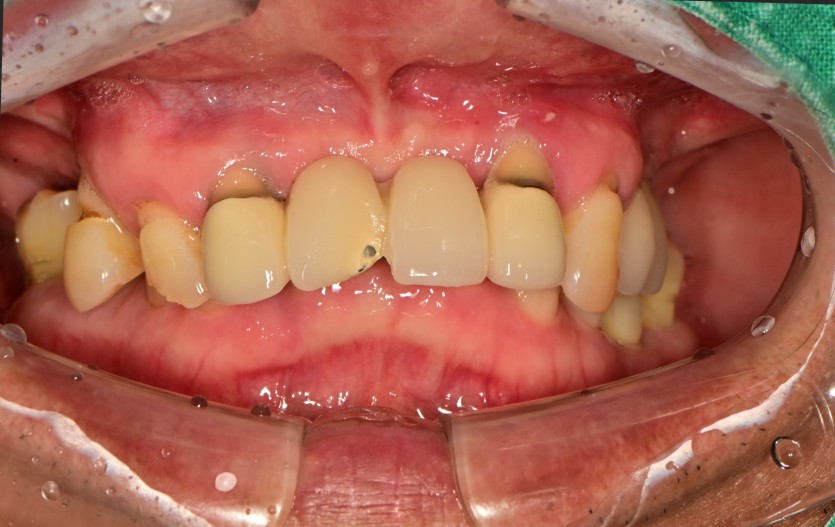

만 60세 상악 전체 임플란트 증례(기존 임플란트 활용)

상악 전체 임플란트 증례입니다.

(타원 임플란트 활용)(하악 일부)

12개의 임플란트로 완성하였습니다.